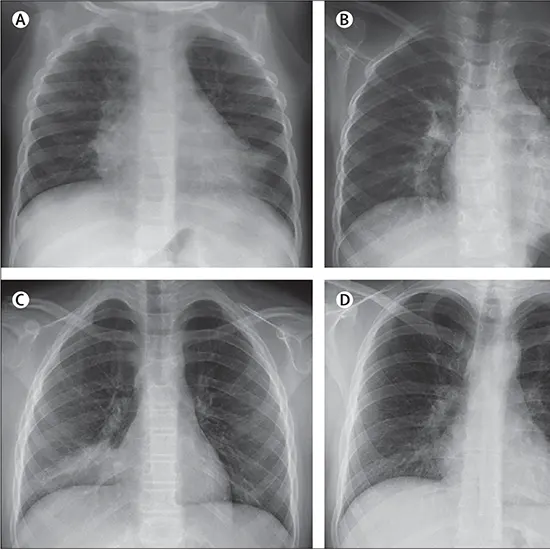

Chest X-ray

By identifying the size and location of the infection, a chest X-ray can help confirm the diagnosis of pneumonia.